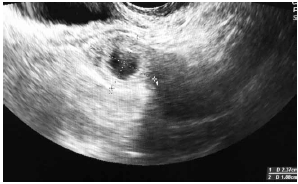

C.V.R.S., 36 anos, G VII P VI (6N) A0, IG cr: 6 semanas,deu entrada no PSGO com sangramento vaginal há cerca de 1 semana. Sem ultrassom prévio. Ao exame físico: especular: colo uterino sem lesões, mínima quantidade de sangue vermelho escuro em fórnice posterior. TV (toque vaginal) bimanual: colo impérvio, grosso, posterior. Ausência de dor à mobilização do colo uterino. Abdome: DB negativo, dor leve à palpação profunda de hipogástrio. Submetida à ultrassonografia transvaginal (imagens a seguir: figuras 1, 2, 3, 4) e beta HCG quantitativo: 9 000 UI/mL. Resultado de beta HCG 24h antes: 7 000 UI/mL.

Figura 4 (zoom de região anexial E; sem visualização de embrião)